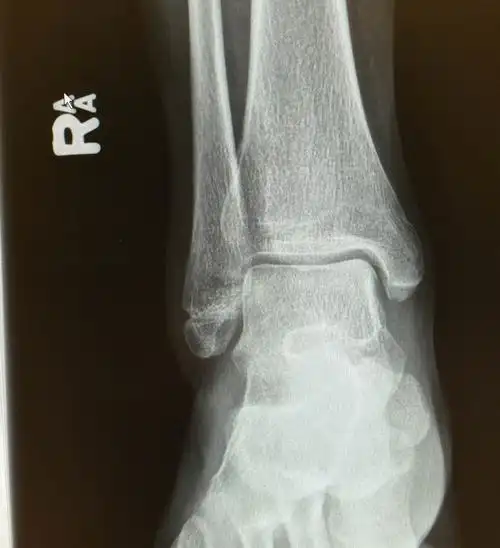

左脚踝骨折,骨裂,手术上钢板